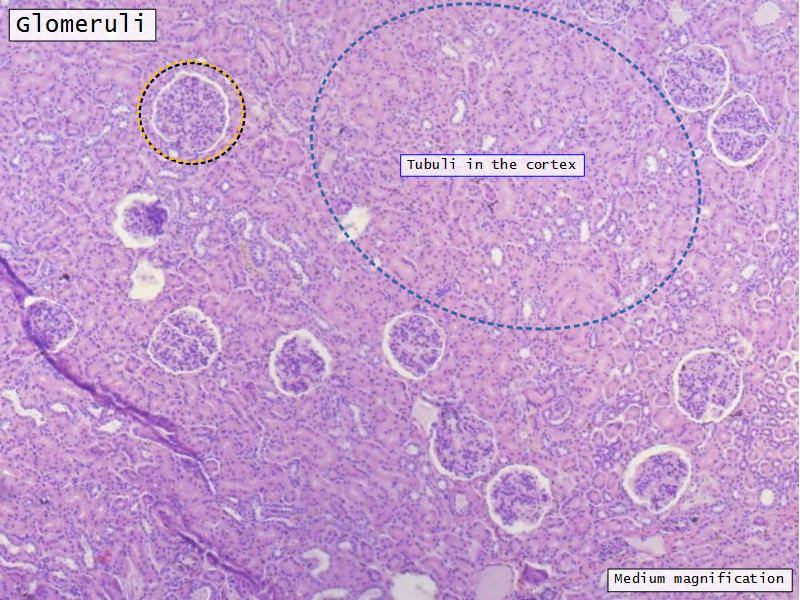

Appearance

- Cortex

- Renal corpuscles

- Convoluted tubules

- Medulla

- Loops of Henle

- Collecting tubules

Kidney lobule

- Group of neprons

- Open into branches

- Same collecting duct

- Not clearly demarcated

- Interlobular arteries/veins